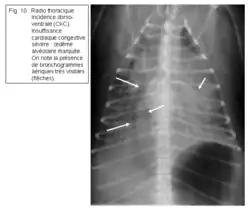

La radiographie est l’examen de choix pour visualiser la congestion : elle se traduit dans un premier temps par des dilatations vasculaires, puis par l’apparition d’œdème pulmonaire, d’abord interstitiel puis alvéolaire (présence de bronchogrammes, cf. figure 10).

Figure 10 : Radio thoracique incidence dorso-ventrale (CKC). Insuffisance cardiaque congestive sévère : œdème alvéolaire marquée. On note la présence de bronchogrammes aériques très visibles (flèches).